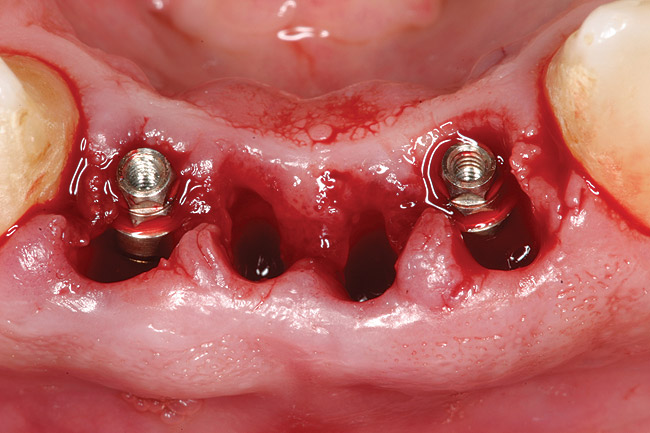

Figure 3a 3  Osteotomies prepared lingually.

Figure 3a

Figure 3  Placement of implants without flap elevation.

Figure 3